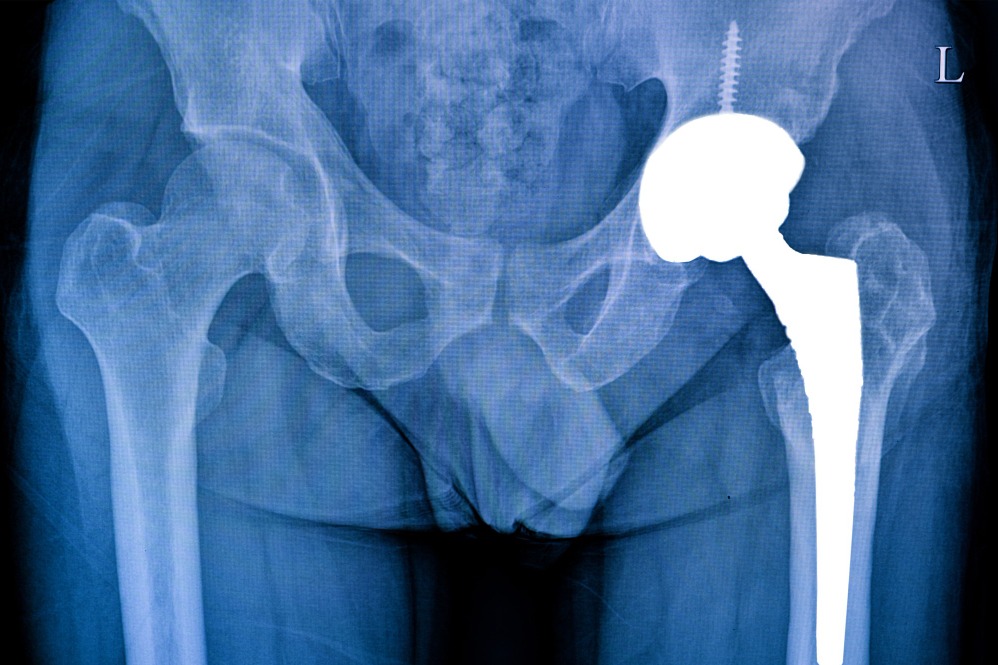

Partial Hip Replacement in Churchgate – A Balanced Approach to Joint Care

Hip injuries don’t always require a complete replacement. For patients where only part of the hip joint is affected, a Partial Hip Replacement can deliver effective results with a shorter recovery period. In Churchgate, Dr. Sujit Korday provides this advanced orthopedic treatment, combining precise surgical skills with personalized patient care.

This procedure replaces the damaged portion of the hip with a high-quality prosthesis while preserving healthy bone and tissue. The result is a smoother joint function, reduced pain, and faster rehabilitation. Dr. Korday’s method focuses on restoring strength and stability while minimizing downtime, helping patients return to normal life more confidently.